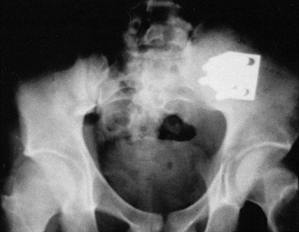

fresh pelvic fractures (Fig. 28.2) (14). We also use this plate to stabilize sacroiliac nonunions (Fig. 28.3, Fig. 28.4, Fig. 28.5, Fig. 28.6 and Fig. 28.7).

Figure 28.4.

A 45-year-old woman with a very painful nonunion of the sacroiliac joint on the left plus symphyseal diastasis. Her initial fixation, months ago, was with an external fixator. Of note, she also had a nonunion of the tibia on the left and an L-5 nerve root deficit. |

Figure 28.5. Three-dimensional reconstructions from CT scans demonstrating the pathology present in Figure 28.4.

Figure 28.6. Three-dimensional reconstructions from X ray demonstrating the pathology in Figure 28.4.